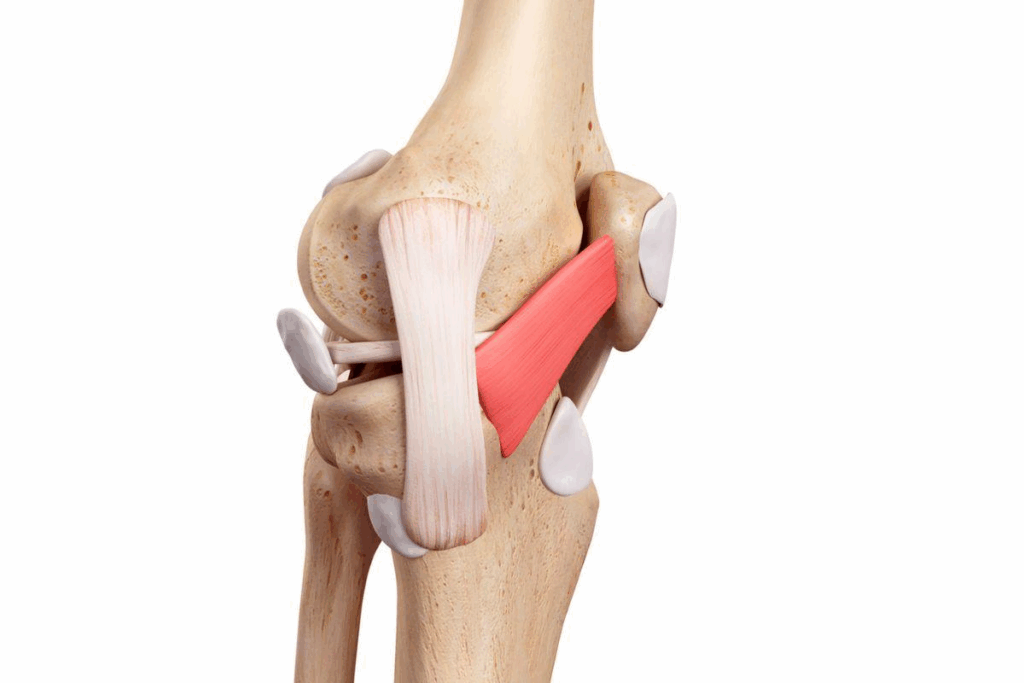

O ligamento patelofemoral medial é uma estrutura fibrosa localizada na parte interna do joelho, que conecta a patela (rótula) ao fêmur, ajudando a estabilizar a articulação.

Sua principal função é impedir que a patela deslize lateralmente, garantindo que ela se mova de forma adequada ao longo do sulco femoral durante a flexão e extensão do joelho.

Esse ligamento é essencial para manter a estabilidade da patela, distribuir corretamente as forças durante movimentos como caminhar, correr ou saltar, e proteger outras estruturas do joelho contra sobrecargas e deslocamentos.